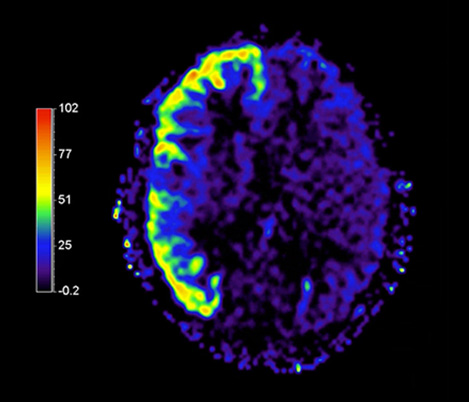

We are continuing with our partners our journey to make MR more accessible1 and definitive2. At ISMRM this year, you will see some more developments that contribute to bringing our vision to life. The need for speed for instance, with Compressed SENSE3, which relies on a heavy sub-sampled acquisition and iterative reconstruction. Come see also our advancements on APT3 (Amide Proton Transfer) a non-contrast technique based on endogenous cellular proteins in tissue, typically present in brain tumors.

APT3 - Non-Contrast technique generating MRI contrast based on endogenous cellular proteins concentration in tissue.